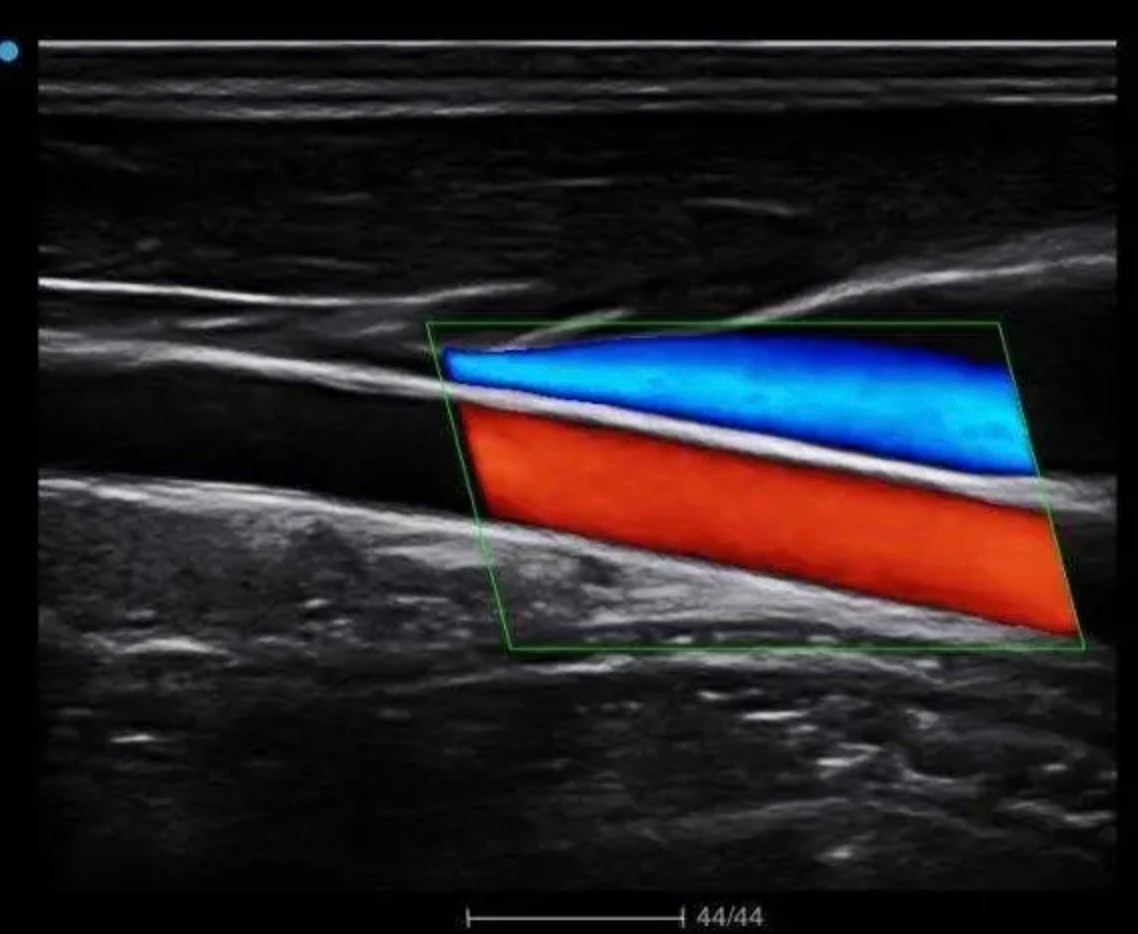

2、通常专科医生多数在大医院,在医疗资源不可及的情况下,可以先做一些检查排除。最简单的是做神经彩超或触及肿块部位的彩超,这样比较容易发现肿瘤。进一步可以做可疑部位的磁共振检查。